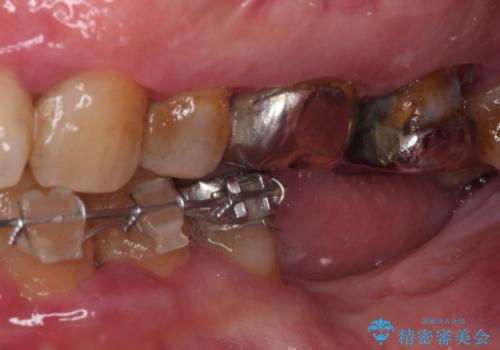

- インプラント治療を前提に下顎の部分矯正を始めたものの、そのまま長い間放置しているとのことで来院された患者様です。

全体的に歯肉が腫れており、歯周病により抜歯をしなければならない歯がある状態でした。

矯正治療を仕上げ、必要に応じて歯周外科処置を行い、適宜インプラントを埋入しながら咬み合わせを回復させていくこととしました。

治療前は磨き残しが多く見られ、全体的に歯肉が腫れている状態でしたが、抜歯の必要な歯を抜いたことで口腔内の環境が改善され、磨き残しも少なくなってきました。